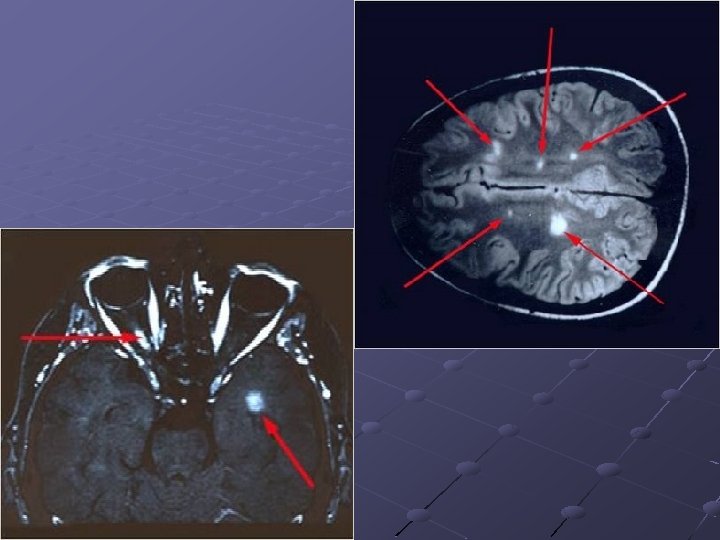

Patologia Áreas multifocais de demielinização Cicatrizes glióticas no SNC e apoptose Lesões em placas (sclérose en plaques) Infiltrado inflamatório perivascular Placas de regeneração (shadow plaques)* Distribuição preferencial na SB, perivascular e periventricular*